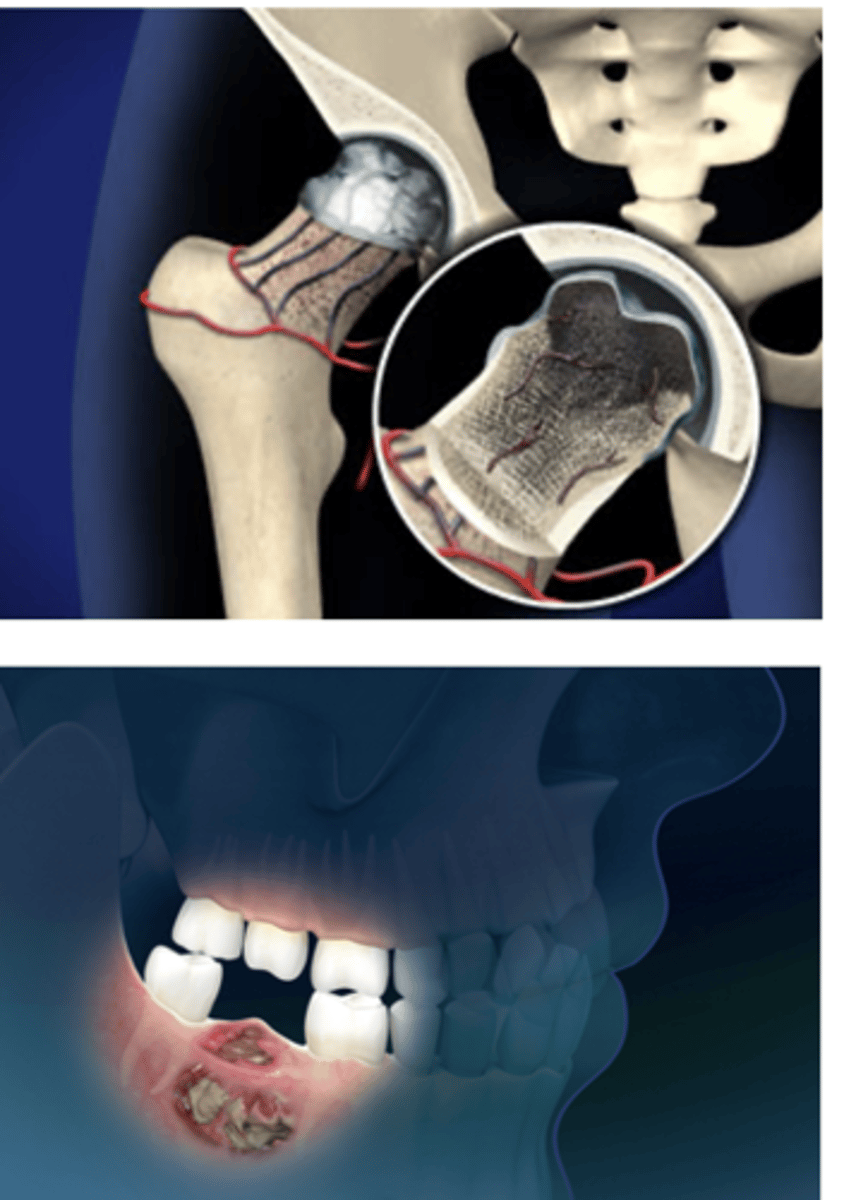

osteonecrosis

Aseptic destruction of a segment of bone due to an interruption in blood flow

Sites with poor collateral circulation (e.g., femoral head) are most commonly affected

Symptoms:

- Depend on location & severity

- Pain with activity (can progress to pain at rest)

Treatment:

- Short-term immobilization or limited weight-bearing

- Exercises

- NSAIDs

- Advanced: total joint replacement

Jaw osteonecrosis risk increases with bisphosphonate therapy